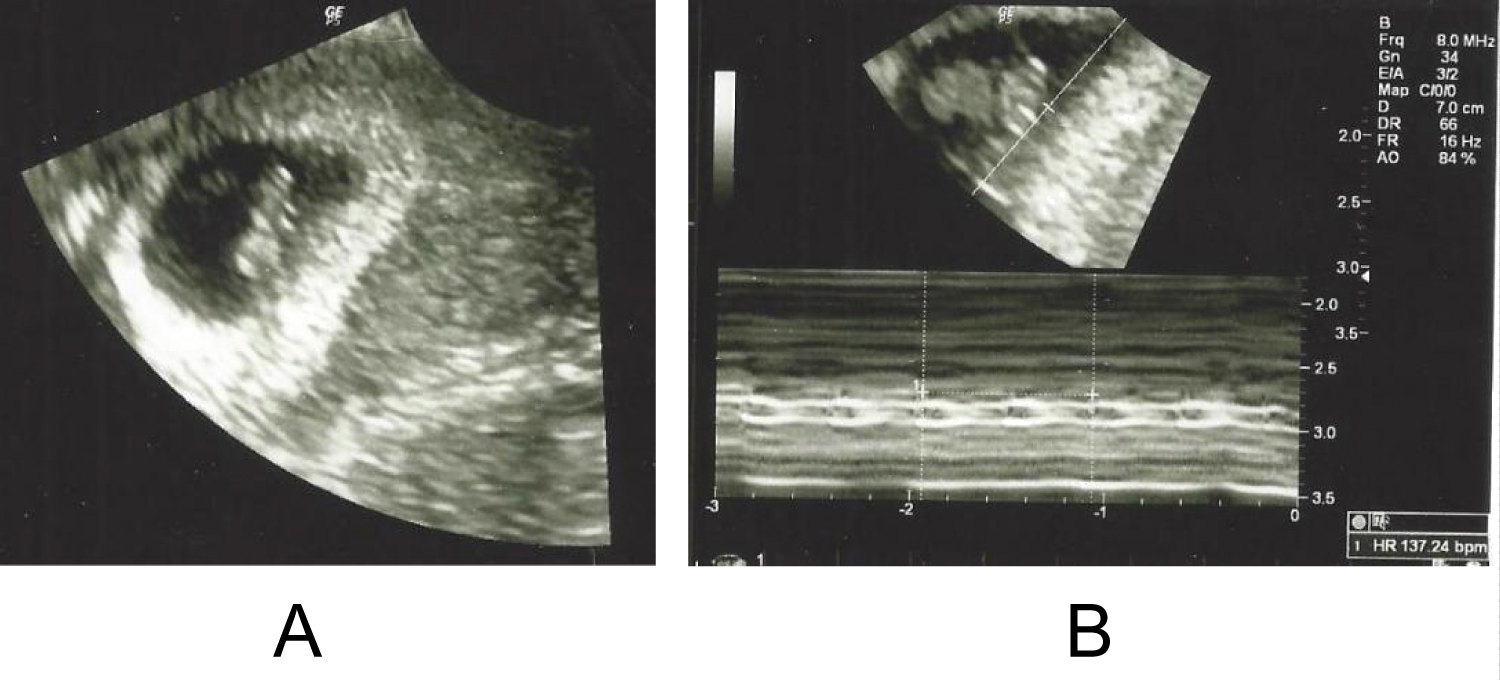

A 35-year-old gravid 1 para 0 presented to her OB/GYN at 7 weeks by known last menstrual period (LMP) for her first prenatal visit. She has a history of hypertension and post-op deep vein thrombosis after an elective peroneal tendon repair. Her ultrasound that day demonstrated single intrauterine pregnancy consistent with her LMP (Figure 1A and Figure 1B). At 12 weeks, the patient had a cell free DNA (cfDNA) test performed that came back abnormal, the result being high-risk. Cell-free DNA is a serum-based screening test for aneuploidies using analysis of cell-free DNA fragments of placental trophoblasts that escape into the maternal circulation [1]. The report suggested this was due to either a vanishing twin, unrecognized multiple gestation or increased risk of fetal triploidy. No further ultrasounds were preformed until 19 weeks.

Figure 1: (A) 7 weeks, first ultrasound photo demonstrating one fetus present in the uterus; (B) 7 weeks, first ultrasound photo demonstrating fetal heart rate. View Figure 1

As shown above in Figure 1A and Figure 1B, it is seen that in the 7-week ultrasound only one fetus is seen in the uterine cavity. Normally when a woman is pregnant with twins you will see 2 fetuses present in the uterus at the 7-week ultrasound. It is extremely rare to miss twins at a 7-week ultrasound, especially when they are diamniotic dichorionic. In Figure 2A and Figure 2B, it is seen at the 21-week ultrasound that 2 fetuses are shown in the uterine cavity for the first time. At this ultrasound growth discordance similar to the 19-week ultrasound was noted between Twin A and Twin B. Research has shown that initial cfDNA test fails (e.g., the results are not reported, indeterminate, uninterpretable, or no-call) have an increased risk of aneuploidy [8]. However, her first MFM consult did not discuss the possibility of a missed twin pregnancy diagnosis for this patient's initial high-risk cfDNA test. A missed superfetation twin pregnancy does explain her initial high-risk cfDNA result and the subsequent recalculated cfDNA being result of insufficient fetal DNA. The redrawn cfDNA test result of low-risk also points to two normal fetuses. On all of the subsequent ultrasounds that were done after 19 weeks there was always a consistent growth difference between the two fetuses but normal interval growth still occurred which is shown in Graph 1. Since there was normal interval growth on subsequent ultrasounds it goes against the idea of fetal growth restriction due to triploidy and points more towards superfetation as the cause for growth differences [5]. The placenta examination post-operatively also points toward superfetation. The second placenta was much smaller and appeared to be "smashed" up against the other more normal appearing placenta. The NICU course of stay and subsequent management of Twin B as being more premature than Twin A also points toward superfetation and not fetal growth restriction.